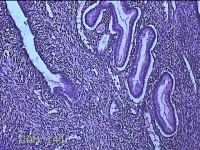

宫颈赘生物

性别

女

年龄

42岁

临床诊断

宫颈赘生物待查?

一般病史

阴道不规则流血15天。

标本名称

大体所见

灰白暗红色肿物1.3x0.7x0.3cm一个,表面糜烂。

图2